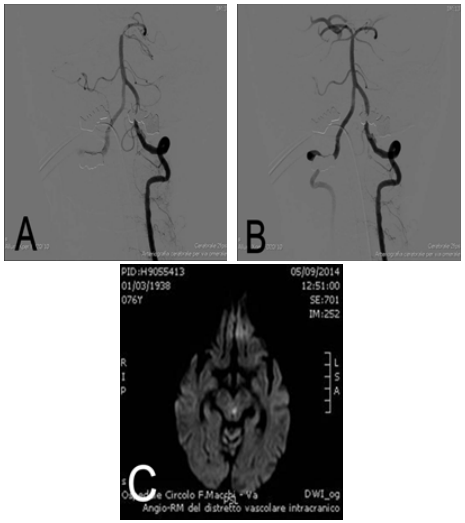

Figure 2 Digital subtraction angiography of midbasilar-distal artery occlusion before (A) and after (B) treatment with mechanical thrombectomy. MRI sequences in DWI (C) shows a mesenchefalic paramedian-left ischemia.

Endovascular treatments were performed within 8 hours of stroke onset (mean time 4 hours, range 2-6) by an Interventional neuroradiologist. Under local anesthesia using a transfemoral approach, a 6 French guide catheter was placed in the proximal vertebral artery. To prevent the occurrence of a thromboembolic event during the procedure, a solution of 2000 international units heparin and 0.9% normal saline (1000mL) were administered in continuous through the guiding catheter. A cerebral diagnostic angiography was performed to assess vessel occlusion and collateral flow to the affected vessel territory. After basilar arterial occlusion was demonstrated, diagnostic catheter was exchanged with a 6F guide catheter (Neuron, Penumbra, California, USA). A microcatheter on a microwire 0.018-inch (Rebar 18, Covidien, California, USA) was introduced into the target vessel. After that, a retrievable stent (in 5 cases Solitaire, Covidien, California, USA; in other 2 cases Revive, Codman, California, USA) was introduced through microcatheter and deployed across the occluded segment. (Figure 1 & 2) After the stent was maintained in place for least 3 minutes, microcatheter and stent were gently pulled back together and withdrawn outside the body through the guide catheter. A control angiogram was performed to assess status of recanalization and possible distal embolic events. If recanalization was unsuccessful, the procedure was repeated, with a maximum of 4 was allowed. In addition to mechanical thrombectomy two patients received an intra-arterial thrombolysis (IAT) with recombinant tissue-plasminogen activator (rt-PA) (60ml and 15ml respectively of Alteplase, ActyliseÒ) and one patient received intra-venous rt-PA thrombolysis (72ml - 0,9ml/kg - of Alteplase, ActyliseÒ) (Table 1 & 2). Recanalization was classified according to the Thrombolysis in Cerebral Infarction (TICI) grading scale.13 TICI grades 3 and 2b were rated as sufficient recanalization and TICI grades 2a to 0 were rated as insufficient. In two cases it was reported a slowdown of circle in the right posterior cerebral artery treated by an intravenous injection of 500mg of acid acetylsalicylic (FlectadolÒ). All patients after procedure were observed for at least 24 hours in an intensive care unit and CT was performed. The NIHSS score was assessed at day 7 by a stroke neurologist. Clinical outcome was assessed at 3 months by a stroke neurologist according to the modified Rankin Scale (mRS) score.14